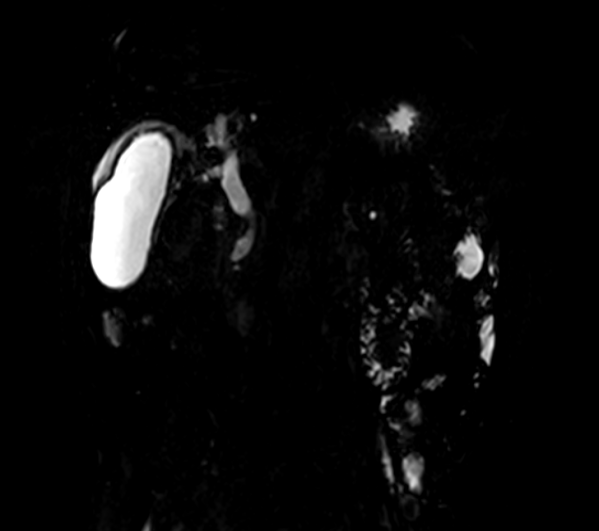

北京清华长庚医院9月2日电 (肝胆胰外科供稿,通讯员 李少东)近日,83岁的老人苏井丰间断腹痛3周家附近医院检查考虑胆囊结石伴胆囊炎、胆管结石、胆源性胰腺炎老人自己说在中青年时期就发现了胆囊结石,但一直未治疗,7年前还做了直肠癌的手术,高血压病史多年,高压最高可到210/180mmHg。这次胆囊结石引起了胆源性胰腺炎,由于老人年龄大,病情复杂,辗转多家医院都不敢接诊最终转诊至北京清华长庚医院肝胆胰外科。

我院李虎城主任医师接诊阅片后,综合评估老人的病情,最终决定为老人行内镜下胆囊胆管取石术+胆囊引流管置入术术中见胆总管扩张,胆囊及肝内胆管正常显影,见胆总管粘膜基本正常,可见多发小碎石,沿导丝经胆囊管进入胆囊,胆囊内见大量泥沙样小颗粒结石、胆汁黏稠,胆囊壁未见明确新生物大量生理盐水冲洗胆囊,见墨绿色泥沙样胆汁流出。退出胆道子镜,取石球囊取出胆总管内结石。手术过程顺利,术中生命体征平稳,术后安返病房。术中字母镜图像如下